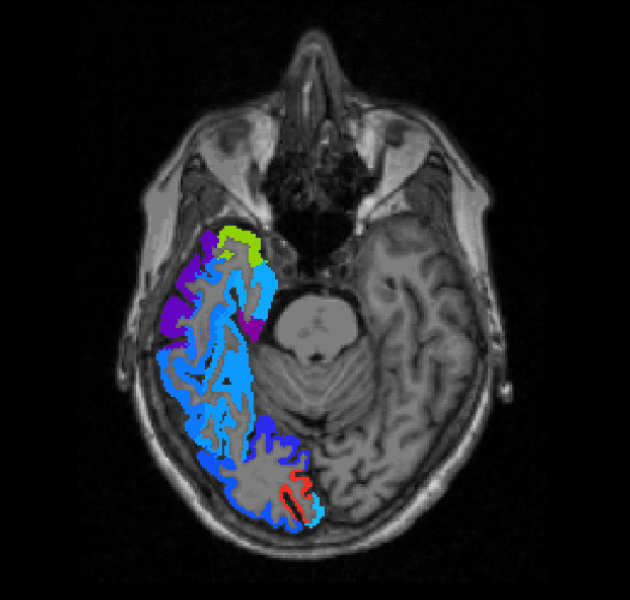

We are investigating imaging biomarkers (diffusion MRI, perfusion MRI, MR Spectroscopy, choline PET) and developing the clinical tools needed to understand brain tumour growth and improve brain tumour diagnosis.

We are developing new machine learning tools to aid clinicians in diagnosing brain tumours through MRI and digital pathology.

We are investigating MRF as a rapid and quantitative technique for characterising brain tumours.

We are investigating the integration of different imaging (DCE-MRI, DWI-MRI, DSC-MRI and PET) techniques for the characterization of tumour tissue.